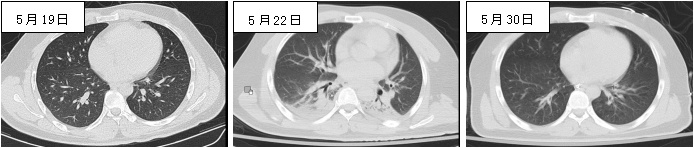

抗菌管理部门结合患者病史、检验检查结果以及微生物标本检验情况等研判,提出:(1)6月3日采集的4瓶血培养标本至6月7日仅1瓶报告检出CRKP,其他3份一直未生长,且之前连续数次血培养结果均为阴性,因此考虑该瓶阳性生长菌株为污染;(2)患者6月5日PCT最高达27.32 ng/mL,但6日早上未更改抗菌药物情况下已降至12.73 ng/mL,下降明显,提示美罗培南抗菌治疗有效,更不考虑CRKP血流感染;(3)该菌株可能是经导管采集血标本污染所致,污染源为呼吸道或皮肤定植的CRKP,因患者自5月27日起所送痰培养中即反复检出CRKP;(4)本次发热原因为新发吸入性肺炎,因5月27日、30日及6月1日肺CT均示已吸收(图 1),6月2日主管医生查房记录患者痰液增多,双肺湿啰音增多,6月5日复查肺CT右下肺有新发渗出,6日CT见右下背段及两下肺后基底段渗出范围扩大(图 2)。综合上述情况,拒绝使用多黏菌素的申请,令主管医生做好反流误吸的相关防控措施,并停用利奈唑胺,只需保留美罗培南(减量为1.0 g/8 h)。6月9日开始体温高峰下降,炎症指标继续降低(图 2),至6月14日神志进一步改善,体温已基本正常(最高37.6℃),转出ICU。

| 图 1 5月22日发生吸入性肺炎,5月30日完全吸收 |